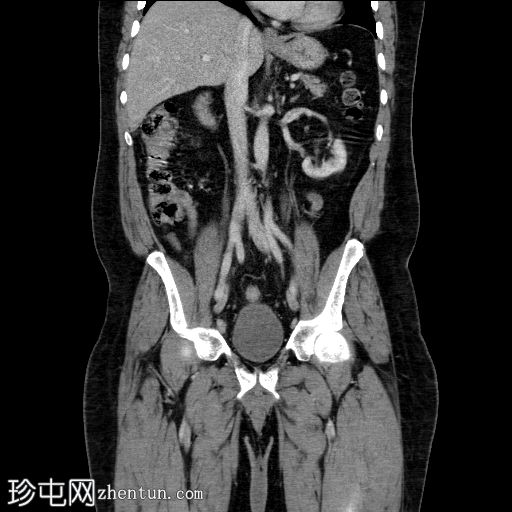

轴位增强扫描(门静脉期)

弥漫性阴茎水肿,阴茎海绵体内积液伴气体,腹股沟淋巴结肿大。